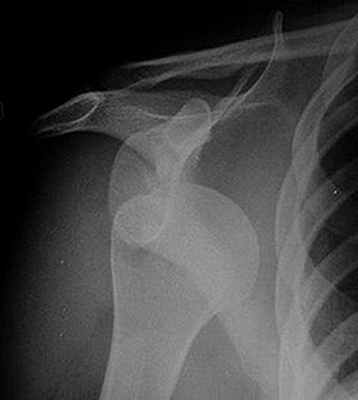

Ощупывание и определение двигательной функции плечевого сустава сопровождаются болью. Движения в дистальных суставах руки сохранены в полном объеме. Движения, как и кожную чувствительность, определять обязательно, поскольку вывихи могут сопровождаться повреждением нервов; чаще других поврежден бывает подмышечный нерв. Не исключено повреждение магистральных сосудов, поэтому следует проверять пульсацию на артериях конечности и сравнивать со здоровой стороной. Ведущим вспомогательным методом исследования при вывихах плеча является рентгенография.

Сначала врач осматривает пациента и узнает обстоятельства, которые привели к травме. Затем пациенту делают рентгенографию в нескольких проекциях. Этого должно быть достаточно, чтобы определить, правильно ли расположена головка кости плеча.

Результаты рентгенографии также показывают, не повреждены ли кости. Вывих плеча может сопровождаться переломом костей. В таком случае это не просто вывих, а переломовывих.

Если рентгенография не дает достаточно данных о повреждении, могут назначить КТ и МРТ. Обследования помогают получить данные о состоянии тканей, связок, костей и мышц